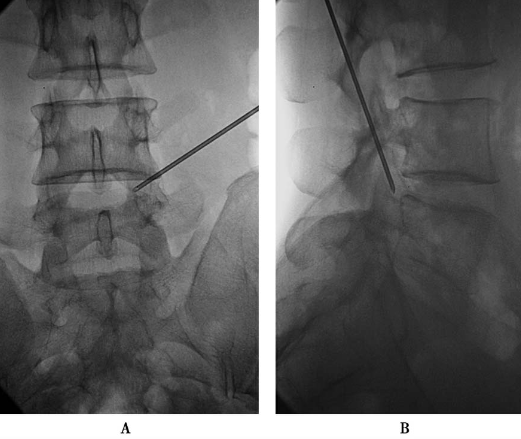

置入2级导杆使头端到达第一靶点(图18)。

图18 置入2级导杆A.前后位透视:头端到达第一靶点;B.侧位透视:侧位透头端抵达L5椎体后上缘。

拔出导丝,将导杆尾端压向腹侧,用手锤敲打导杆尾端,使导杆头端在L5椎体后缘潜行到达第二靶点(图19)。

图19 拔出导丝,将导杆尾端压向腹侧,用手锤敲打导杆尾端,使导杆头端在L5椎体后缘潜行到达第二靶点A.侧位透视头端抵达L5椎体后缘;B.前后位透视头端到达第二靶点。